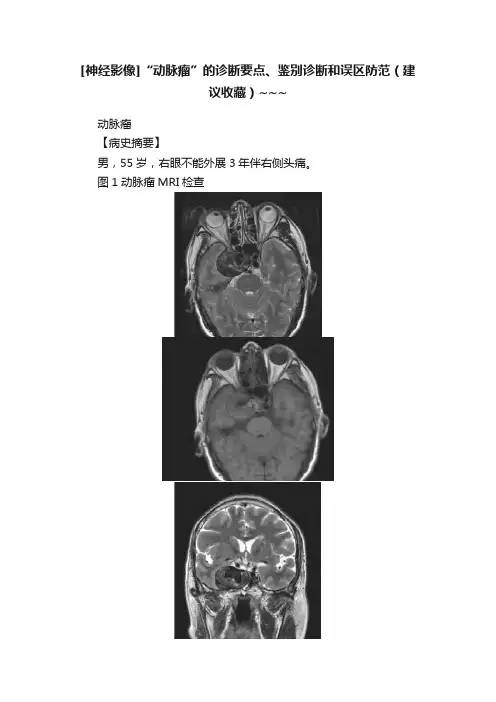

[神经影像]“动脉瘤”的诊断要点、鉴别诊断和误区防范(建议收藏)~~~动脉瘤【病史摘要】男,55岁,右眼不能外展3年伴右侧头痛。

图1动脉瘤MRI检查【影像所见】图1A、B、C,横轴面T2WI、T1WI及冠状面T2WI显示右侧海绵窦旁可见一类圆形的异常信号,呈混杂短及等T2、短及等T1信号,边界清楚。

图1D、E,增强扫描示病变内侧中心部分呈明显强化,边缘部分可见强化。

图1F,MRA示该病变与右侧颈内动脉海绵窦段关系密切。

【诊断和分析】本病例诊断为颈内动脉瘤。